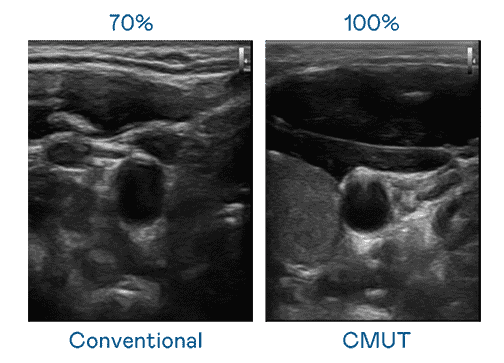

CMUT 技术是一种用电容式微机电元件来产生超音波讯号的技术。。。与传统 PZT 压电式技术相比,,,CMUT 频宽增加 30%,,更宽频的超音波讯号让影像解析度大幅提升,,,是实现高影像品质医疗超音波扫描、、、促进精准医疗发展的关键技术。。

超音波影像的解析度高低,,,,首先取决于探头能发出的讯号频宽。。z6mg·人生就是博 CMUT 可提供高清晰的超音波讯号,,提供高频宽、、高灵敏度、、影像纹理细节更高的超音波影像,,协助医护人员缩短影像判读时间及利用精准的医疗影像进行诊断。。